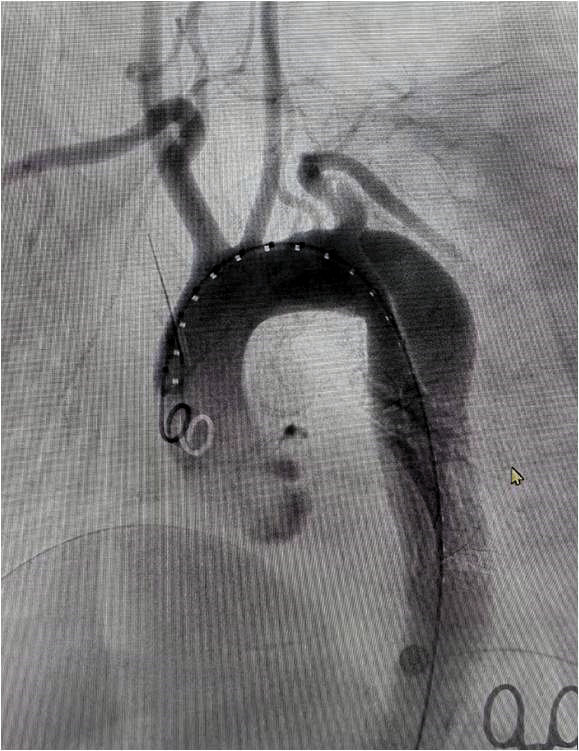

体外开窗:打开支架前端,褪下部分外管和软鞘,放开前端部分主体支架,根据术前测量结果,在支架外标记左侧椎动脉开口完成体外开窗,将支架撤回软鞘和外管内。

建立分支导丝通路:经左侧股动脉引入导丝导管,从股动脉引出,建立分支导丝通路。

释放支架主体及分支并后扩分支支架:从右侧股动脉引入超硬导丝至升主动脉,沿着超硬导丝送入输送系统并上推至升主动脉,助手配合牵拉分支导丝,使分支支架进入左锁骨下动脉,并使支架窗口对准左侧椎动脉开口,经造影确认支架定位准确后,快速释放主体支架,助手配合牵拉导丝释放分支支架。撤出支架主体,由左侧股动脉导入8-80球囊扩张支架支架,沿左侧股动脉入金标导管至升主动脉,造影显示支架有效封堵夹层破口,无移位和内漏现象发生,左椎动脉与左锁骨下动脉血流通畅,手术圆满成功。